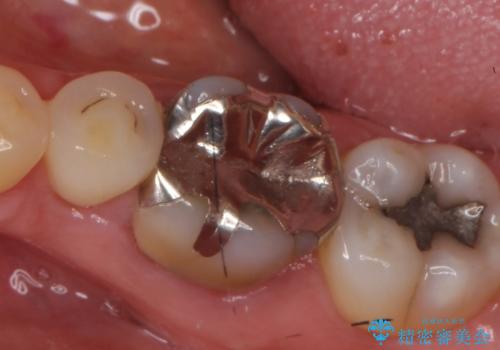

- 他院にて左下6の再根管治療を勧められ当院にいらっしゃった方の症例です。

再根管治療終了後、オールセラミッククラウンにて補綴を行いました。